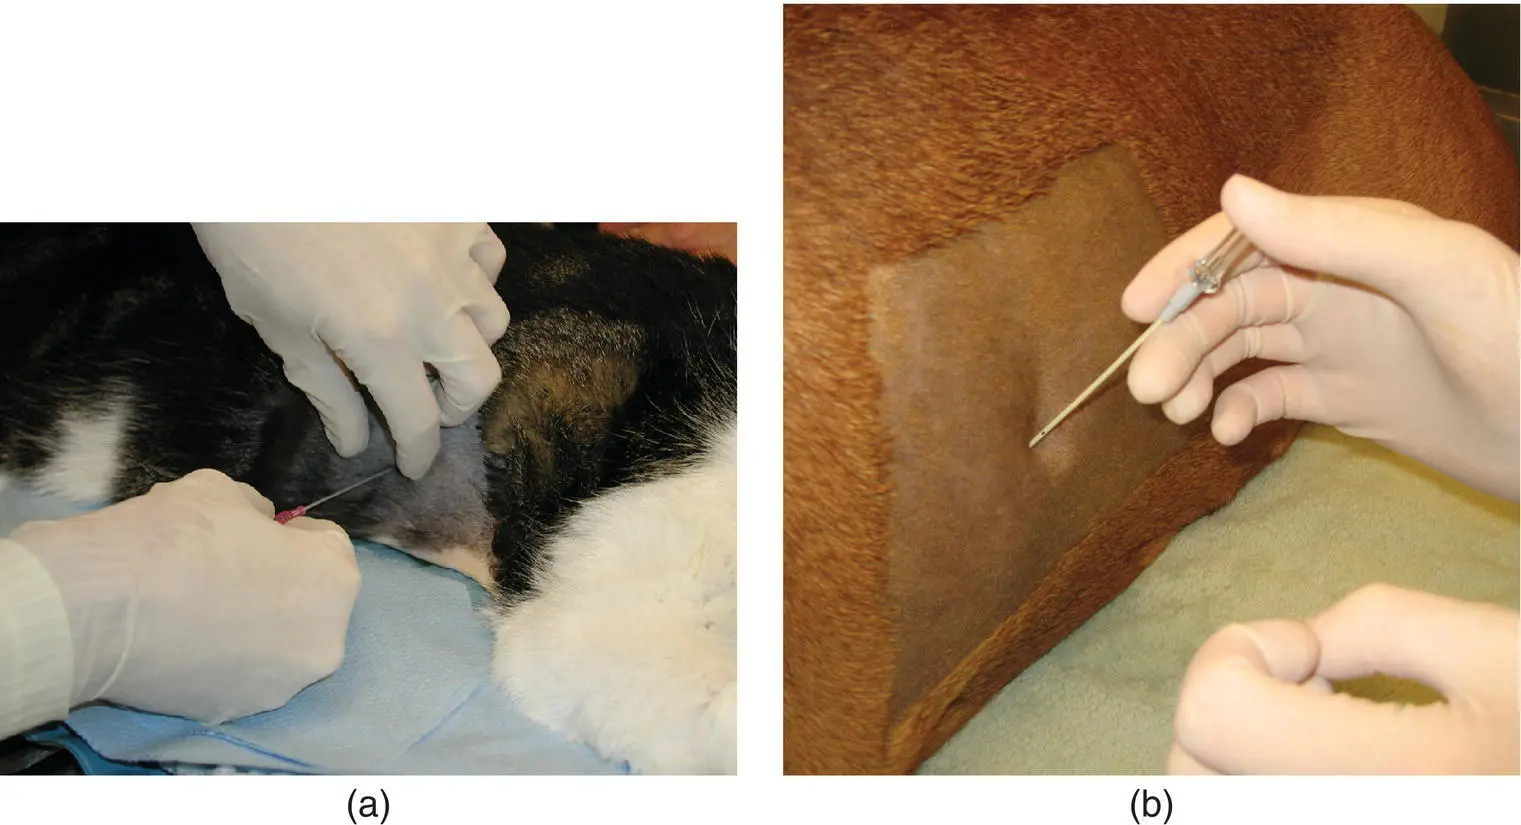

Figure 2.24 Ultrasound guidance is used to obtain a lung biopsy using a Temno biopsy needle.

Percutaneous lung biopsy can be obtained with use of an ultrasound‐guided biopsy needle in the anesthetized patient. This is performed more commonly in dogs than in cats. A surgical preparation is performed, and a 16–18 gauge Temno™ biopsy needle (Merit Medical Systems, South Jordan, UT) is guided into the lesion to obtain a 2 cm core tissue sample for histopathology ( Figure 2.24). After either aspiration or biopsy, the animal should be placed in lateral recumbency with the side of the aspiration facing downward for 15–30 minutes to promote the development of a clot or seal at the aspiration site. Typically, an ultrasound is performed after the procedure to screen for hemorrhage or pneumothorax. Visualization of the normal “glide” sign as the lung slides across the pleura rules out one of these complications. An increase in respiratory rate or effort or detection of absent lung sounds near the site of aspiration would indicate hemorrhage or pneumothorax and the need for intervention.